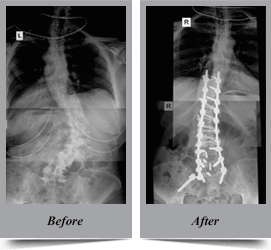

Congenital Scoliosis

Congenital scoliosis is the lateral curvature of spine that occurs in children